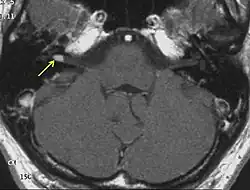

Ein Akustikusneurinom (kurz AKN oder AN) ist ein gutartiger Tumor, der von den Schwann’schen Zellen des vestibulären Anteils des VIII. Hirnnerven, des Hör- und Gleichgewichtsnerven (Nervus vestibulocochlearis), ausgeht und im inneren Gehörgang, bei größerer Ausdehnung auch im Kleinhirnbrückenwinkel gelegen ist. Das Akustikusneurinom ist histologisch eigentlich als Vestibularis-Schwannom zu bezeichnen. Die Bezeichnung Akustikusneurinom ist aber klinisch üblich.[1] Es ist der häufigste Kleinhirnbrückenwinkeltumor.

Diagnose des Akustikusneurinoms

Eine sichere Diagnose liefert nur die histologische Untersuchung nach einer Gewebeentnahme. Erstmals röntgenographisch dargestellt wurden Akustikusneurinome mit Erweiterungen des inneren Gehörgangs durch Salomon Eberhard Henschen (1910) und Hendrik Willem Stenvers (1917).[4] Klinisch relevante Tumoren können heute mit einer Magnetresonanztomographie (MRT) zuverlässig detektiert werden.